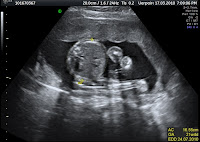

Funnily enough, we could never get a good image of her whenever we did an ultrasound. She’ll have her hands covering her face all the time, legs kicking and kicking, making it impossible for our doctor to scan us a good image of her. All we knew throughout my 41+ weeks of pregnancy and told by Dr. Ah-Chai was that the baby has an egg-shaped head, big belly, long limbs and large feet.